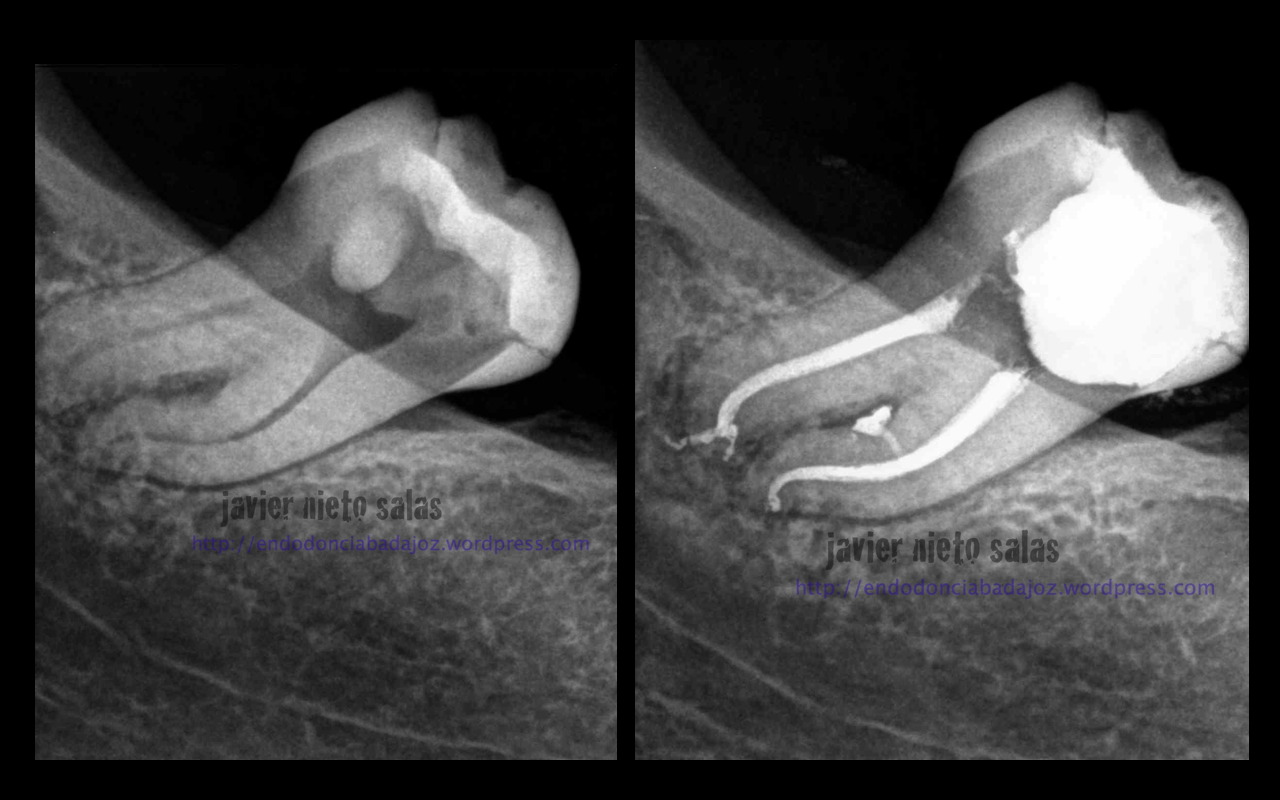

Este segundo caso, después de estudiar la Rx, vemos un defecto en la furca, y ¿porqué no puede ser el origen las endotoxinas y demás productos de las bacterias intraconducto que colonizan un conducto lateral en ese nivel medio? ( 15% según Vertucci)

Volvemos a ver a la paciente a los 9 meses y vemos como la lesión ha regenerado correctamente y la lesión en furca va desaparecido.